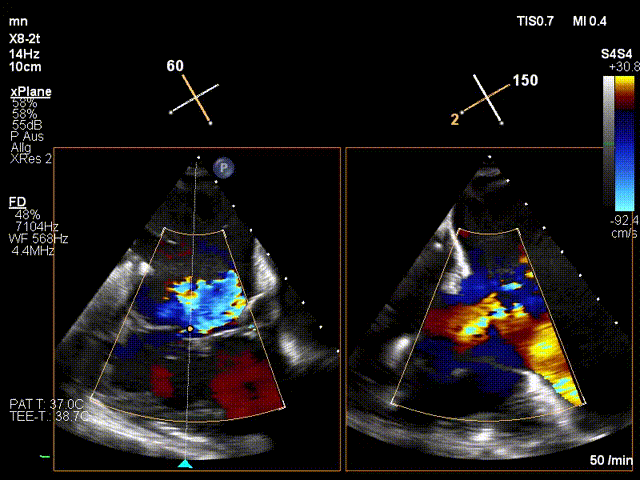

近日,德國(guó)慕尼黑大學(xué)Jörg Hausleiter教授團(tuán)隊(duì)成功應(yīng)用LuX-Valve Plus經(jīng)血管三尖瓣置換系統(tǒng)救治了一例因三尖瓣大量反流導(dǎo)致的右心衰竭患者,術(shù)后超聲顯示人工三尖瓣位置固定滿意,瓣架穩(wěn)定,無反流和瓣周漏?;颊咴谑中g(shù)室即刻拔除氣管插管,血流動(dòng)力學(xué)改善顯著,LuX-Valve Plus經(jīng)血管三尖瓣置換系統(tǒng)的治療效果優(yōu)異。

手術(shù)在全麻狀態(tài)下進(jìn)行。在加拿大圣保羅醫(yī)院的Anson Cheung教授的指導(dǎo)參與下,術(shù)者采用經(jīng)右側(cè)頸靜脈入路的方式將輸送器送入患者心臟內(nèi),在TEE及DSA引導(dǎo)下調(diào)整輸送器頭端角度,使得輸送器與三尖瓣瓣環(huán)平面垂直。在輸送器進(jìn)入右心室后釋放室間隔錨定裝置,而后釋放瓣葉夾持件(2個(gè)耳片結(jié)構(gòu))成垂直狀態(tài)。在TEE及DSA確定夾持件固定至三尖瓣葉根部且位于右室側(cè)后釋放人工瓣心房側(cè)盤片。隨后調(diào)整瓣膜同軸性以及室間隔錨定件位置(貼合室間隔),前推藏針管并固定,進(jìn)而釋放室間隔錨定裝置,并再次確認(rèn)瓣膜位置、穩(wěn)定性及同軸性,合攏輸送鞘后撤出輸送器,完成LuX-Valve Plus人工三尖瓣瓣膜的植入。

LuX-Valve Plus經(jīng)血管三尖瓣置換系統(tǒng)本次“出海”圓滿完成,術(shù)后Jörg Hausleiter教授對(duì)LuX-Valve Plus經(jīng)血管三尖瓣置換系統(tǒng)的器械性能和治療效果大為稱贊,認(rèn)為L(zhǎng)uX-Valve Plus的手術(shù)體驗(yàn)非常好。術(shù)后即刻超聲顯示三尖瓣反流消失,血流動(dòng)力學(xué)改善顯著,患者恢復(fù)快。Anson Cheung教授也肯定了LuX-Valve Plus術(shù)中操作的便捷性,認(rèn)為L(zhǎng)uX-Valve Plus容錯(cuò)率高,對(duì)術(shù)中影像的依賴較小,后期希望可以更多的應(yīng)用LuX-Valve Plus三尖瓣置換系統(tǒng)于臨床實(shí)踐,讓更多的三尖瓣重度反流患者盡早獲益,改善預(yù)后。